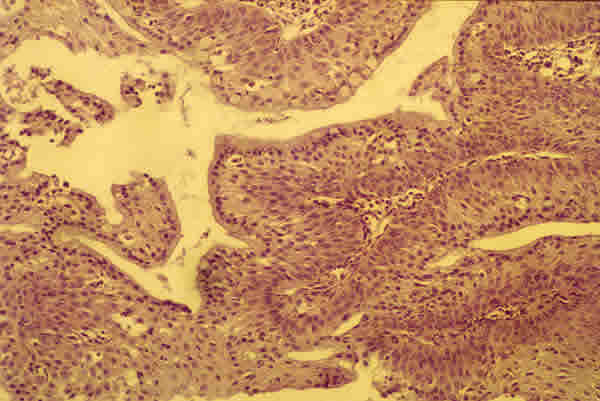

Histológicamente, la lesión muestra numerosas ramificaciones papilares vascularizadas con un epitelio acantósico (fig. 2). No hemos encontrado koilocitosis (célula escamosa madura con vacuolización perinuclear) pero sí la presencia de un VPH tipo 18 demostrado por la técnica de la reacción en cadena de la polimerasa (PCR). Se aplica colirio de mitomicina C postoperatorio al 0,04% cuatro veces al día durante 7 días, repitiendo el ciclo tres veces. Tras 22 meses de seguimiento permanece sin signos de recurrencia (fig. 3).

Fig. 2. Sección histológica del papiloma escamoso. A destacar los centros fibrovasculares rodeados por un epitelio escamoso acantósico (H-E 100x).